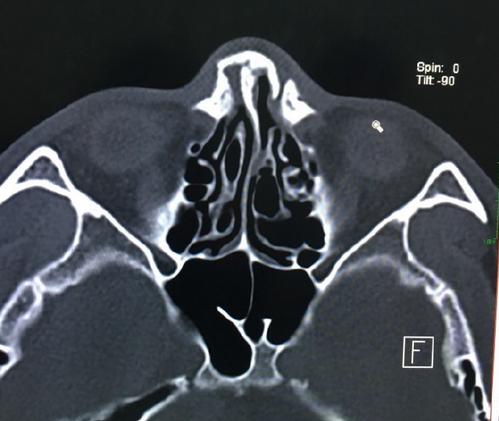

这是一番战前的CT报告:双侧鼻骨、左侧上颌额突及鼻中隔骨质连续性中段,双侧上颌窦内示高密度影。余未见明显异常。

从CT可以看出,他的鼻子已经偏了,并出现连续性中段。结论是:双侧鼻骨、左侧上颌额突骨折;鼻中隔骨折;双侧上颌窦积液或炎症。